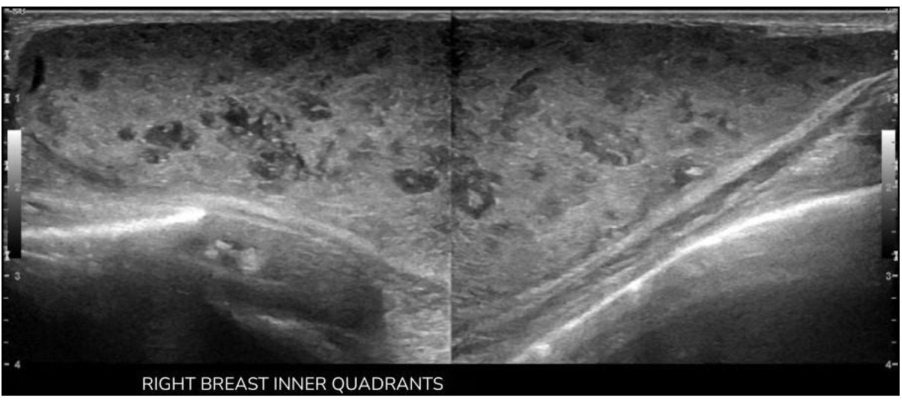

因肿块体积大、影像学表现可疑,行超声引导下 14G 针芯穿刺活检,组织病理示:囊肿壁由复层鳞状上皮构成,囊内充满层状角蛋白,符合表皮样包涵囊肿诊断(图 4)。

图4 (A)H&E染色,10倍放大:可见大量层状角蛋白及散在红细胞,符合表皮样包涵囊肿的典型成分;(B)H&E染色,4倍放大:可见大量角蛋白条索。